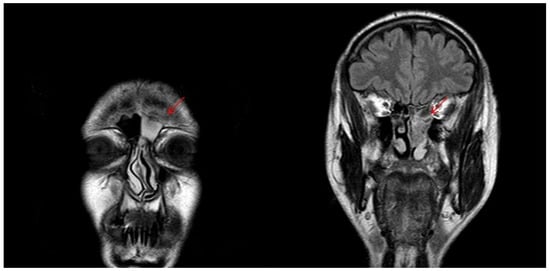

4.9. Olfactory Neuroblastoma (ONB)

- Kawaguchi, M.; Kato, H.; Tomita, H.; Mizuta, K.; Aoki, M.; Hara, A.; Matsuo, M. Imaging Characteristics of Malignant Sinonasal Tumors. J. Clin. Med. 2017, 6, 116. [Google Scholar] [CrossRef]

- Sivalingam, J.; Sarawagi, R.; Raghuwanshi, S.; Yadav, P.K. Sinonasal Neoplasia – Clinicopathological Profile And Importance of Computed Tomography. J. Clin. Diagn. Res. 2015, 9, TC01–TC04. [Google Scholar] [CrossRef]

- Oztürk, E.; Sağlam, O.; Sönmez, G.; Cüce, F.; Haholu, A. CT and MRI of an unusual intranasal mass: Pleomorphic adenoma. Diagn. Interv. Radiol. 2008, 14, 186–188. [Google Scholar] [PubMed]